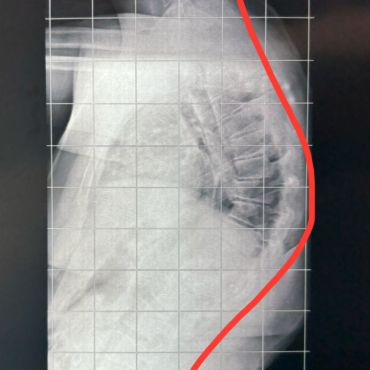

A plagiocefalia posicional também chamada de achatamento posicional ou plagiocefalia deformacional, refere-se à uma alteração do formato do crânio que ocorre na parte posterior (região parieto-occiptal) em decorrência de pressão continuada neste local. A frequência vem aumentando desde a década de 90, quando foi dada a orientação de dormir de barriga para cima pela Academia Americana de Pediatria. A pressão persistente sobre um dos lados da cabeça nos meses iniciais predispõe o bebe à ocorrência da plagiocefalia posicional. Nesse caso, não há fusão das suturas do crânio (craniossinostose), apenas a deformação do crânio em um ponto onde há pressão predominante.

É necessário fazer o diagnóstico diferencial entre a plagiocefalia deformacional, que é uma alteração posicional e a craniossinostose, em que ocorre a fusão (ossificação) precoce das suturas (articulações) do crânio. Na maioria das vezes o diagnóstico é clínico, ou seja, através da história e exame físico do bebê. Em certos casos atípicos, pode ser necessária a realização de exames de imagem. O exame realizado geralmente é a tomografia computadorizada com reconstrução em três dimensões. Nele é possível identificar a fusão precoce das suturas, o formato e proporções do crânio e outras alterações que podem estar associadas.